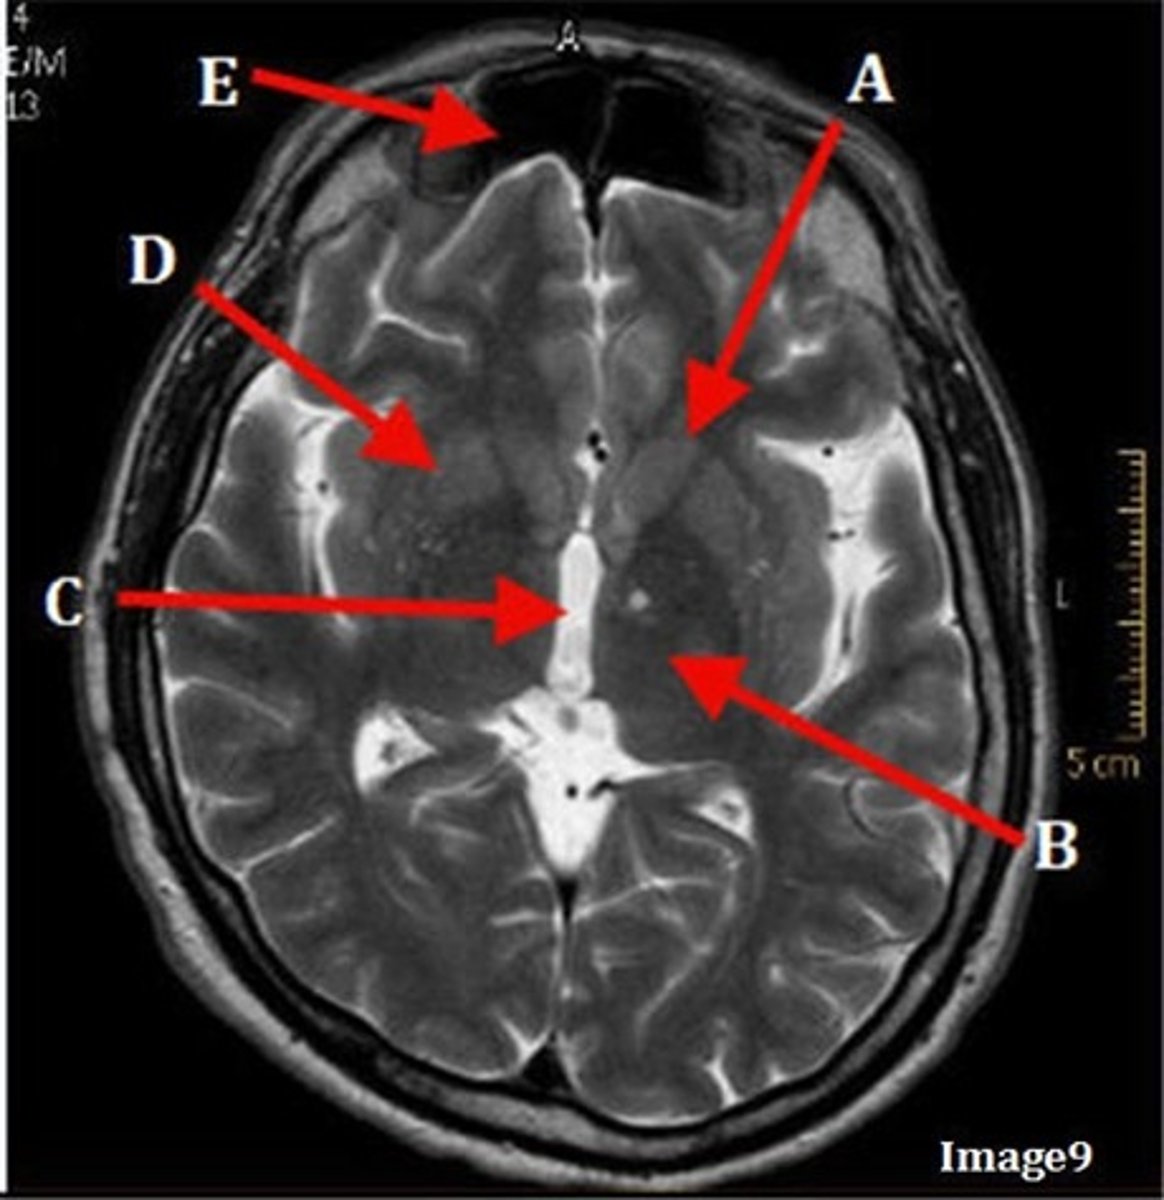

A

caudate nucleus

B

thalamus

C

third ventricle

D

lentiform nucleus

E

frontal sinus

A (region)

dark band is called?

basal ganglia region

internal capsule

posterior horn of lateral ventricle

anterior horn of lateral ventricle

white matter

F

gray matter